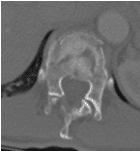

48 yo Female had a sledding injury when she landed on her buttocks following a fall. She felt a “pop” and immediate back pain. She was able to walk briefly, but quickly incapacitated by pain. Her examination suggested an injury to the lower thoracic spine. She was neurologically intact. She had uncontrolled pain. X Rays and CT scan of the patient showed fracture of T12 vertebral body.

The fracture was stabilized by Minimal Invasive spine surgery with percutaneous pedicle screws in T11, 12 and L1 and rod fixation.